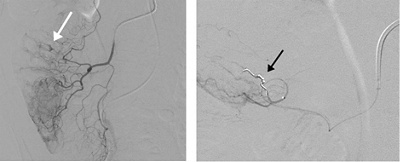

Angiographischer Nachweis

Angiographischer Nachweis einer Dickdarmblutung aus einem Divertikel (weisser Pfeil), welches nachfolgend mittels Metallspiralen (Coils) ausgeschaltet wurde (schwarzer Pfeil).